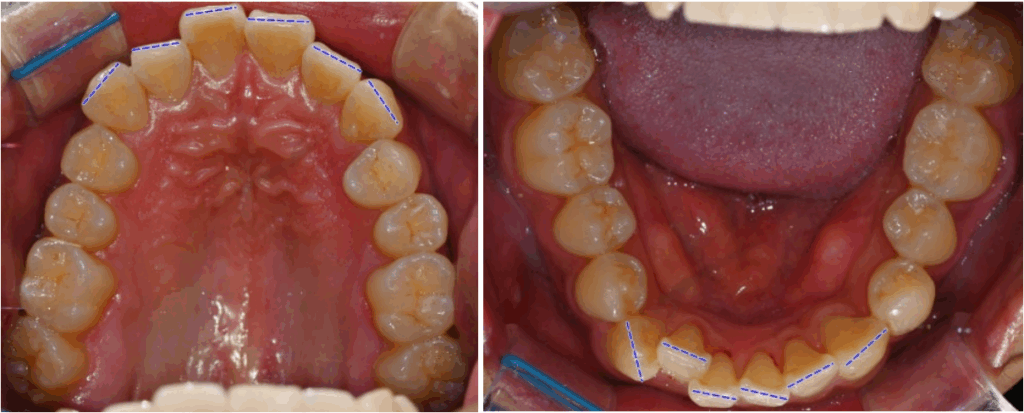

위아래 어금니 간 폭경의 비율이

부조화를 보인 것을 볼 수 있습니다.

더불어, 왼쪽 비강의 협착과

상악동 염증 소견이 보입니다.

치근의 길이는 양호한 것까지

확인한 뒤 다음과 같은

계획을 수립할 수 있습니다.